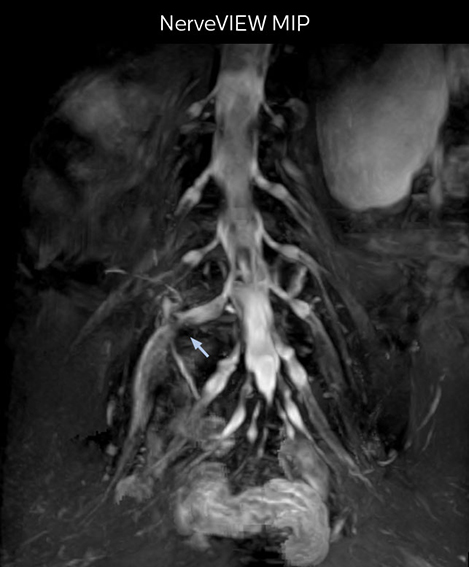

At Northern Fukushima Medical Center in Japan, excellent MRI visualization of nerves helps support confident diagnoses and informs surgical treatment decisions for patients with lower limb symptoms. MRI technologist Tanji and orthopedic surgeon Dr. Yabuki share how direct nerve visualization with the 3D NerveVIEW method adds information when diagnosing atypical herniations. The additional insights changed their way of working and benefit their patient care, as illustrated by some clinical examples.

“In patients with lower extremity neurological symptoms, NerveVIEW helps us to determine the disease matching the patient’s symptoms by directly visualizing the nerves. We use the sequence mainly, when there is suspicion of intraforaminal stenosis, extraforaminal stenosis or lateral disc herniation, which is often based on routine T2- and T1-weighted images. Additionally, the excellent depiction of the course of nerves makes NerveVIEW a good navigator when applying treatment such as block therapy or surgery.”

“In such case, we would then browse through axial T2-weighted MR images slice by slice and mentally reconstruct the actual situation based on both radiculography and MRI. Fortunately, NerveVIEW can now very well show nerve courses and presence of nerve compression or edema in one single image series.” “We have often seen NerveVIEW directly depict details of the nerve compression that were not observed by radiculography. Therefore, we think that with NerveVIEW we can reduce the number of invasive examinations, especially for some patients with lumbar plexus symptoms.”

The key concept in MR neurography, Dr. Yabuki stresses, is the ability to directly visualize spinal nerves, versus inferring the presence of pathology indirectly. “Before NerveVIEW, we estimated compression of the nerve by looking for the presence or absence of fat signal on other MR images,” he says.

“For example, in sagittal images, when the presence of fat is observed in the intervertebral foramen, it suggests that there is a margin around the nerve. Similarly, the absence of fat indicates that the nerve is being compressed. So, we used to deduce nerve compression indirectly. With NerveVIEW, however, we can observe the condition of the nerves directly, regardless of the presence or absence of fat. We always prefer such direct observation of anatomy over having to make an inference about it.”

“Although symptoms of typical disc herniation and atypical hernia are very similar, the actual site of herniation is different. It is therefore important to characterize the nerve’s condition both inside and outside of the intervertebral foramina. “Conversely, if we see no abnormality in NerveVIEW, we can assume at least that there is no severe condition that requires surgery. Like this, it can help us avoid unnecessary surgery. NerveVIEW can have a tremendous impact in this way.”

“NerveVIEW is really useful for those cases where a nerve disorder is strongly suspected based on the clinical examination but our regular MRI images do not show any findings. These atypical herniations and spinal canal stenosis, occurring in 5% to 15% of the total lumbar herniation/stenosis cases are our main target when using NerveVIEW,” says Dr. Yabuki.